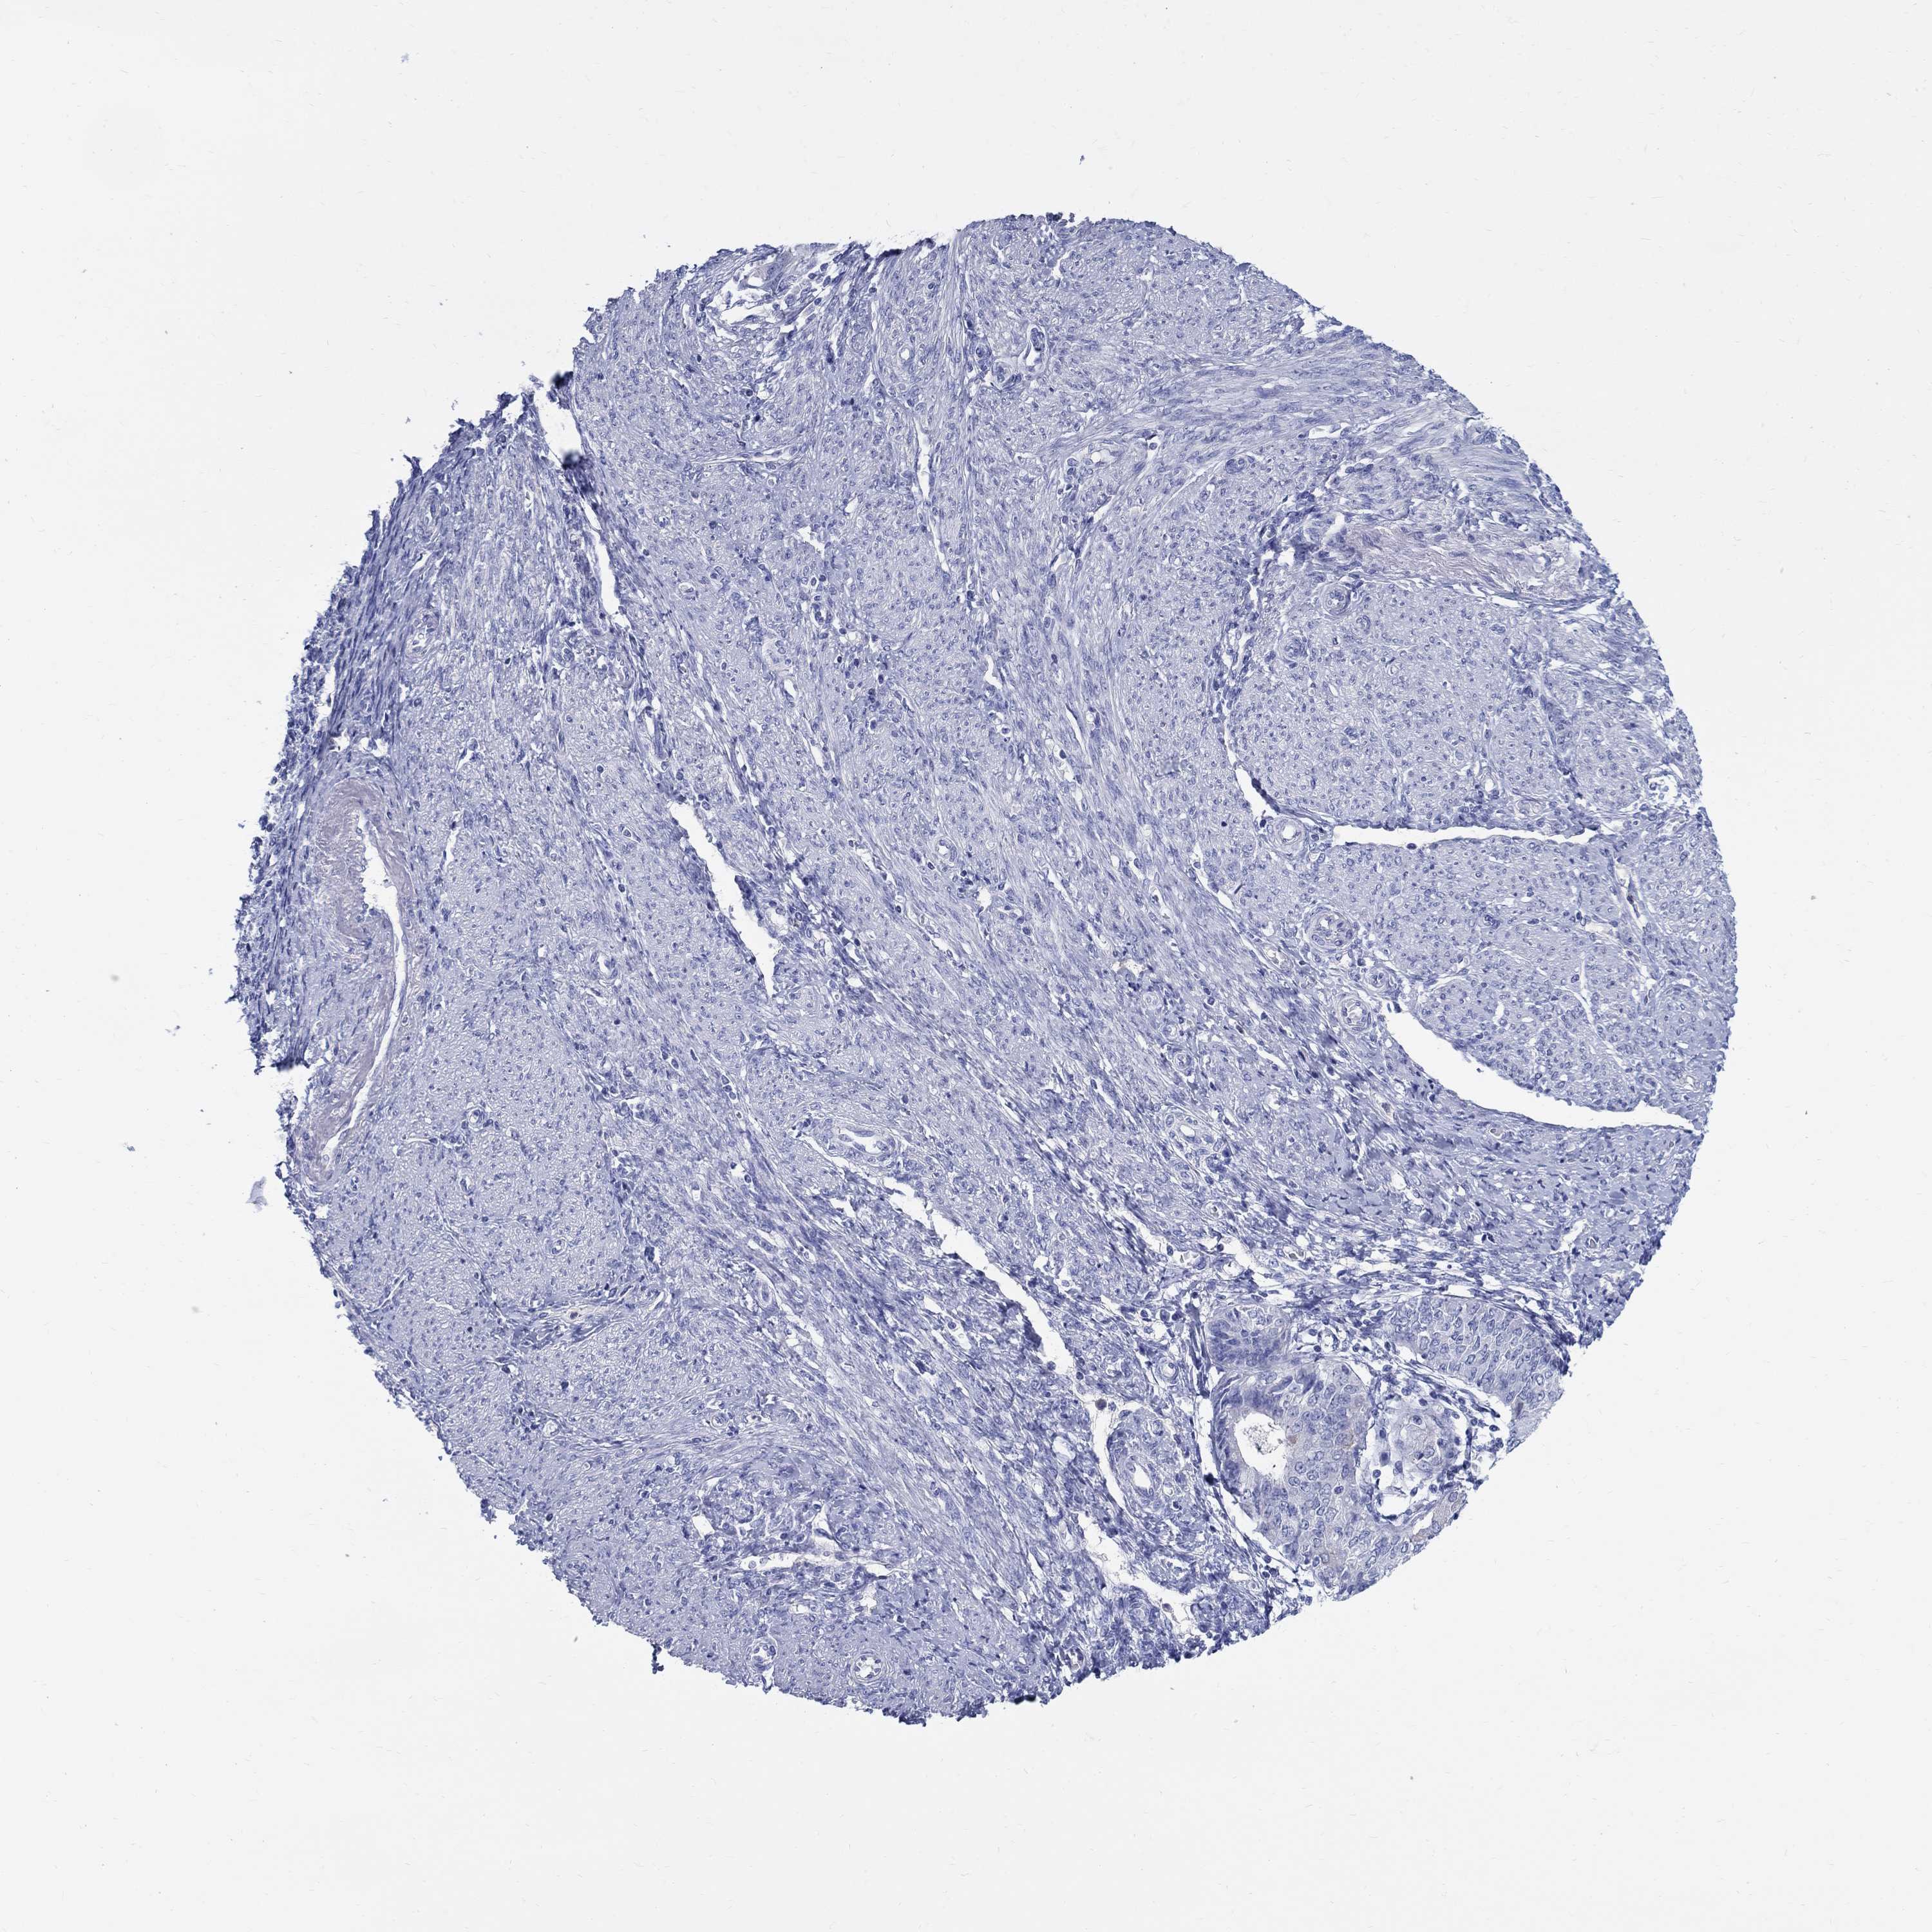

ENDOMETRIAL CANCER - Protein expressioni

A mouse-over function shows sample information and annotation data. Click on an image to view it in a full screen mode. Samples can be filtered based on level of antibody staining by selecting one or several of the following categories: high, medium, low and not detected. The assay and annotation is described here.

Note that samples used for immunohistochemistry by the Human Protein Atlas do not correspond to samples in the TCGA dataset.

Antibody stainingi

Antibody staining in the annotated cell types in the current human tissue is reported as not detected, low, medium, or high, based on conventional immunohistochemistry profiling in selected tissues. This score is based on the combination of the staining intensity and fraction of stained cells.

Each image is clickable and will lead to virtual microscopy that enables deeper exploration of all samples and also displays staining intensity scores, fraction scores and subcellular localization as well as patient and tissue information for each sample.

Antibody HPA045725

Antibody CAB079745

Staining

High

Medium

Low

Not detected

Intensity

Strong

Moderate

Weak

Negative

Quantity

>75%

75%-25%

<25%

None

Location

Nuclear

Cytoplasmic/membranous

Cytoplasmic/membranous,nuclear

Adenocarcinoma, NOS